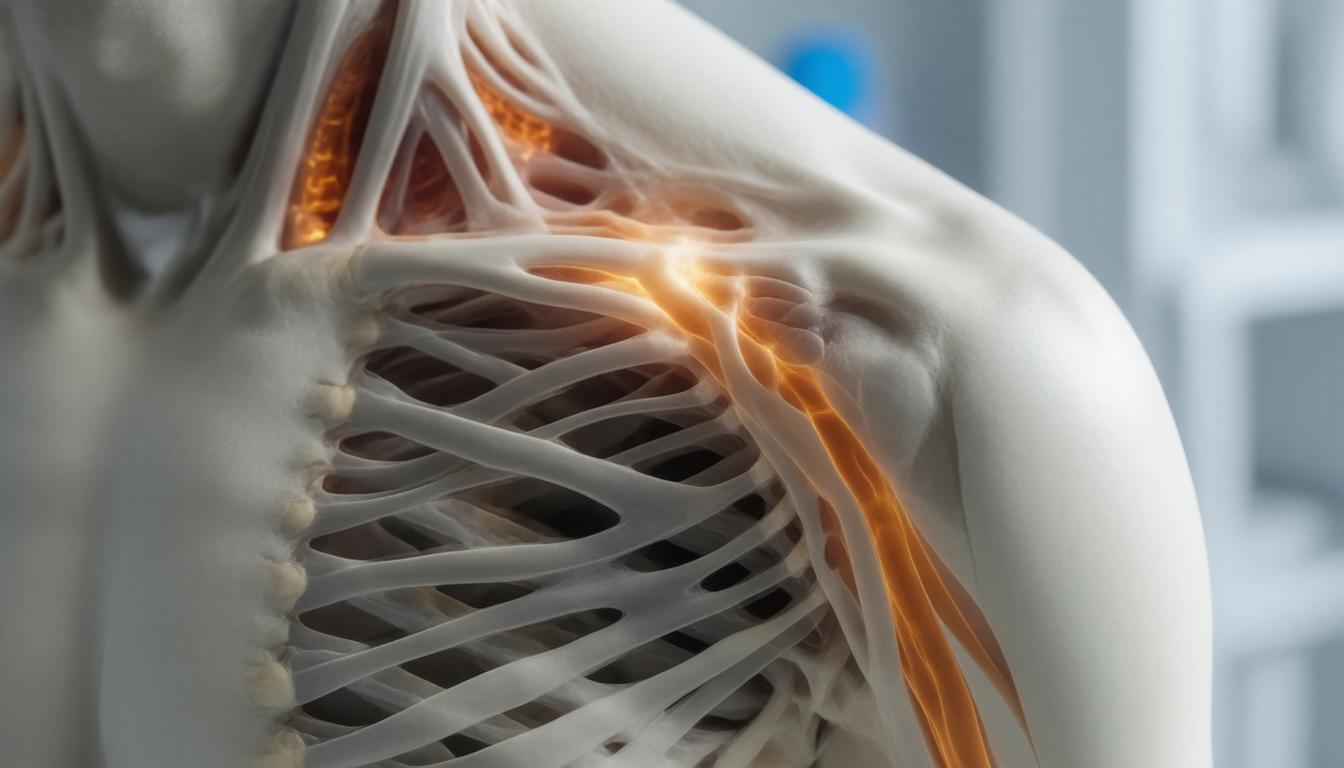

Symptomen en diagnose van peesontsteking

Als je het idee hebt dat je schouder echt niet meer doet wat je wilt, dan is de kans groot dat je te maken hebt met peesontsteking in de schouder. Maar wat zijn nou eigenlijk de symptomen? Nou, vaak komen mensen met een pijnlijke, stijf aanvoelende schouder, en dat kan echt knap vervelend zijn. Je weet wel, die momenten dat je je hand omhoog probeert te doen of zelfs je shirt aan wilt trekken, en ineens geeft je schouder een duidelijke ‘nee’. Het voelt alsof je een zware rugzak om je schouder hebt hangen, ook al ben je gewoon aan het zitten. Het is geen pretje, dat staat vast. Vaak hoor je dan dat je het beste even moet afwachten, maar dat kan best frustrerend zijn.

Maar hoe weet je nou of het daadwerkelijk een peesontsteking is? Vaak zal een specialist een paar simpele tests doen, zoals je arm omhoog tillen en kijken hoe ver je komt zonder in elkaar te krimpen van de pijn. Soms kan een echo of zelfs een MRI nodig zijn om alles goed in beeld te krijgen. Maak je niet te druk, het klinkt erger dan het is; die onderzoeken zijn meestal vrij eenvoudig en kunnen je heel veel duidelijkheid geven. Nou, als je denkt dat je in dit schuitje zit, weet dan dat je niet alleen bent. Veel mensen ondervinden dit, en er zijn talloze manieren om het aan te pakken. Dus ademen, en laten we samen verder kijken naar de oorzaken en vooral de oplossingen.